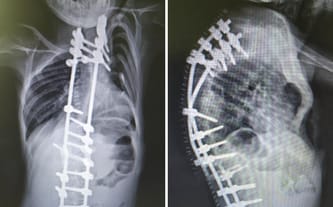

Mnogie wrodzone wady rozwojowe, skolioza, ostra niewydolność oddechowa płucna w następstwie zabiegu chirurgicznego poza klatką piersiową